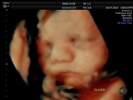

Fotografías de ecografías 4D HD/5D

Haga click sobre las imágenes para ampliar